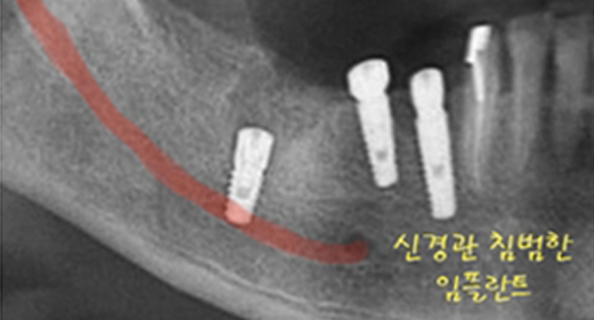

신경이 손상된 사례

신경관 손상으로 마비된 부위

임플란트 부작용 발생 원인은 대부분 정확한 위치에 임플란트가 식립되지 않았기 때문입니다.

- 수술시 신경손상의 위험이 항상 존재하며, 다른 치아 및 구조물에 손상을 줄 가능성도 존재